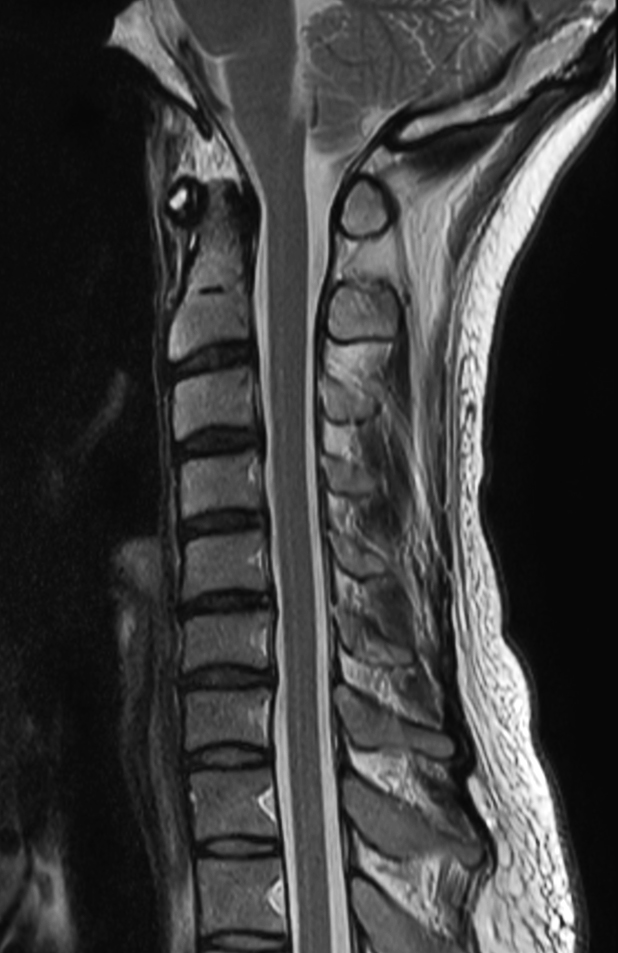

Sagittal T1w TSE

Sagittal T2w TSE